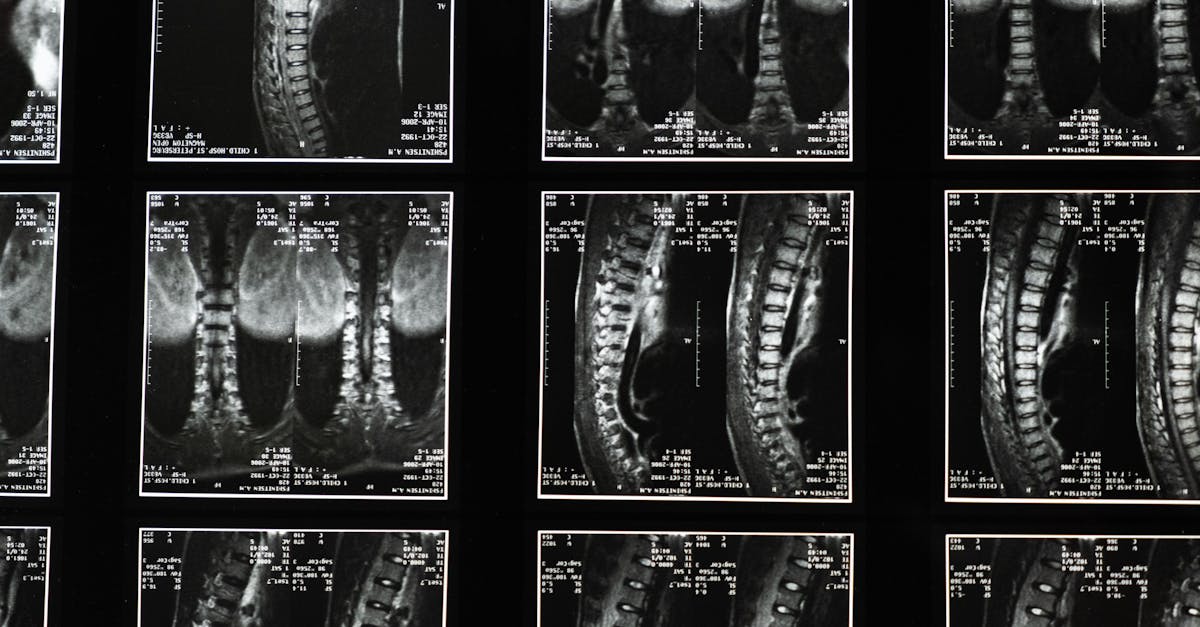

Sciatica is a common condition affecting many individuals, characterized by discomfort that radiates along the sciatic nerve. Various underlying problems can lead to this pain, including herniated discs and spinal stenosis. Pulse Align offers a holistic approach that effectively targets these issues, providing natural relief and supporting neuromuscular health. In this article, we will explore how Pulse Align’s methods promote balance, posture improvement, and overall wellness for those suffering from sciatica.

Understanding Sciatica and Its Causes

Sciatica often results from conditions such as piriformis syndrome, which occurs when the piriformis muscle irritates the sciatic nerve, or from degenerative changes in the lumbar spine that lead to lumbar pain. This nerve can become compressed or irritated, causing pain that radiates from the lower back down through the leg. To manage these symptoms effectively, it’s crucial to understand the root causes of discomfort.

The key to TAGMED’s neurovertebral decompression lies in its application of a controlled, progressive traction force on the spine. This method systematically increases the space between vertebrae, effectively relieving pressure on intervertebral discs and nerve roots. As space is created, better fluid circulation occurs in the targeted area, leading to decreased inflammation and pain relief. This process provides a reliable, non-invasive solution for individuals grappling with chronic back pain and related symptoms.